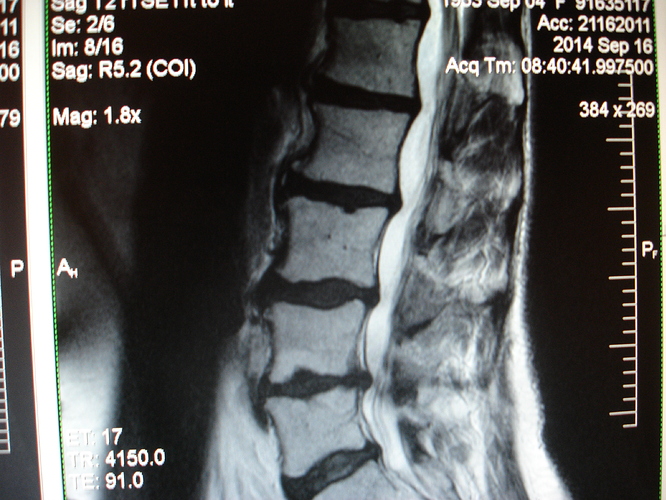

I just added some photos but I did it wrong.....I'll try to add them to this discussion. I'm a little concerned that my discs look different from the MRI pics we got two years ago. I don't know what I'm doing so I won't add any more. I looked at the cd of my sacrum and I can't make heads or tails out of it. In about a week I'll get the radiologist's written report--that will explain everything because I'm in lala land looking at the cds.

FWIW your discs will change through out the day dramatically. Also so you don't go crazy for the next week wondering even though you were naughty and peeked, I'll tell you now.

I do have a CD of the sacrum, too, but I wouldn't know what pic I should use. The written report will give me all the answers.